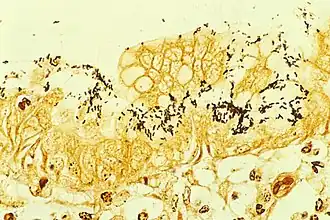

Pro nalezení Helicobacter pylori v tkáních se využívá různých typů tkáňového barvení – Gramovo barvení, Giemsovo barvení, kombinace hematoxylinu a eosinu, barvení dusičnanem stříbrným nebo akridinová oranž. Helicobacter pylori lze v tkáni najít i pomocí mikroskopu s fázovým kontrastem.